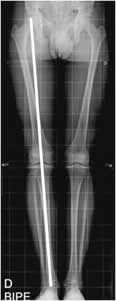

Fig 96. Eje mecánico.

Rx AP. Línea entre el centro de la cabeza femoral y el centro de la tróclea astragalina, que cruza las espinas tibiales.

Fig 97 A. Eje mecánico.

A y B: Rx AP. El eje mecánico forma ángulo de 3º con la vertical en A y de 6º con el eje del fémur en B.

Fig 97 B. Líneas tangenciales.

Rx AP. Relación entre las superficies articulares tibiales superior e inferior, con ángulo de vértice medial.